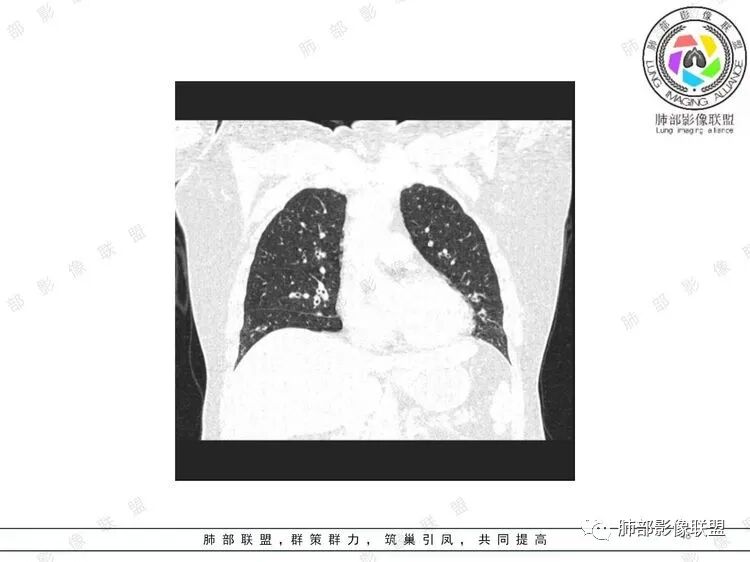

胸CT:双中下肺支气管壁明显增厚,双下肺胸膜下可见实变区。部分病变呈楔形影。

老年女性,咳嗽咳痰低热20天,双肺野散在结节影,随机分布,双肺下叶支气管血管束增粗,支气管管腔狭窄,胸膜下结节斑片影,临床有血尿,痰培养白念阳性,低氧血症。血管炎抗体阴性。从影像看主要侵犯的是血管,血管壁增厚,血管炎抗体阴性不大支持,患者有血尿,考虑膀胱肿瘤引起转移,但是膀胱彩超没发现占位,估计血尿是膀胱炎引起。从影像看考虑侵袭性曲霉菌病?血管炎?实在没有思路。

双肺支气管管壁弥漫性增厚,管腔狭窄,下叶为主,伴多发高密度结节影,边缘模糊,双肺支气管血管束明显增粗,临床症状咳嗽低热,有血尿,首先考虑血管炎

支气管壁增厚,两下肺为主,沿支气管血管束分布斑片状、结节状病变,中轴间质增厚。疾病谱可能有:1.气道来源疾病:结核、曲霉、支原体等;2.间质来源疾病:血管、淋巴系统。结合有血尿,使用激素后尿色变淡、抗生素治疗效果差等病史,考虑血管炎可能性大。

影像上:多发结节沿血管分布;双下叶支气管血管束简直增厚,偏血管,支气管通畅

加上结节的分布,支持血管相关病变

累及范围广泛:肠系膜血管?膀胱